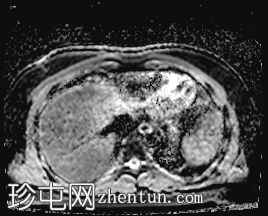

轴位

T2加权像

T1低信号,T2低信号为主的脾脏肿块,内部可见T2高信号分隔,呈进行性强化。肿块中央可见星状瘢痕。

脾脏硬化性血管瘤样结节性转化(SANT),9.8 cm肿块

顾名思义,脾脏硬化性血管瘤样结节性转化(SANT)是一种纤维性血管病变。本病例展示了SANT的一些典型影像学特征,包括边界清晰的病灶,中央可见瘢痕,以及呈放射状进行性强化。这些特征使得术前MRI诊断较为明确。尽管SANT是一种良性病变,但大多数患者仍需行脾切除术以明确病理诊断。